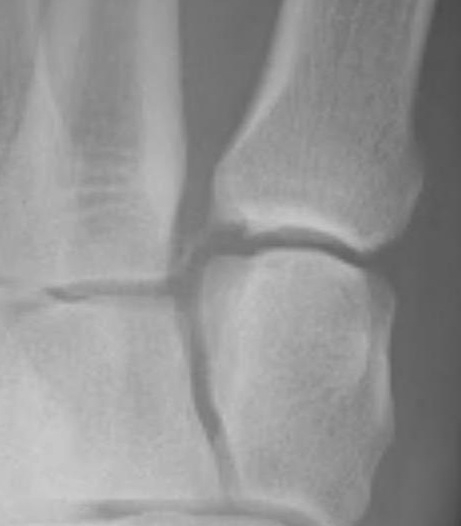

Widening of the medial cuneiform - 2nd metatarsal distance, inter-metatarsal diastasis, fleck sign, increased inter-cuneiform distance

3. Second metatarsal Fleck sign - avulsion of Lisfranc ligament from base of 2nd metatarsal

4. Widening of inter-cuneiform distance